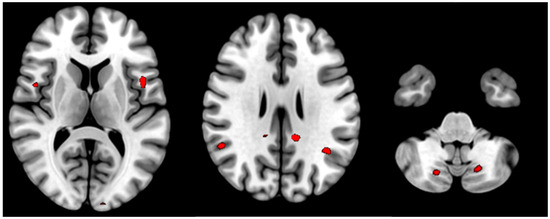

| T | Puncorr | Number of Voxels | Peak MNI Coordinate | |

|---|---|---|---|---|

| Posterior cingulate cortex (L) | 4.06 | <0.000 | 14 | −12 −42 28 |

| Posterior cingulate cortex (R) | 3.32 | 0.001 | 2 | 6 −44 50 |

| Supramarginal gyrus (L) | 3.37 | <0.000 | 23 | −38 −54 30 |

| Supramarginal gyrus (R) | 3.49 | <0.000 | 22 | 52 −50 22 |

| Opercular part of Precentral gyrus (L) | 3.77 | <0.000 | 12 | −46 8 8 |

| Opercular part of Precentral gyrus (R) | 3.47 | 0.001 | 11 | 48 4 10 |

| Cerebellum Posterior Lobe (8) (L) | 3.33 | 0.001 | 67 | −18 −68 −42 |

| Cerebellum Posterior Lobe (8) (R) | 3.25 | 0.001 | 34 | 18 −70 44 |